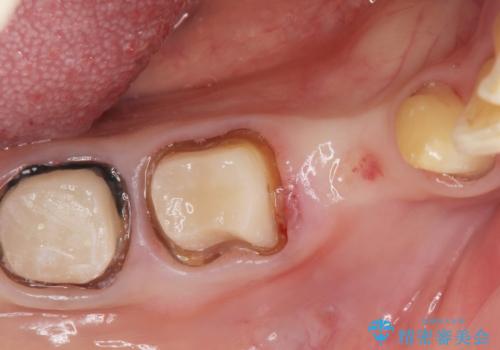

- 他院で右下小臼歯が保存不可能と言われ来院。当院の判断でも残念ながら抜歯となり、欠損部は抜歯後ブリッジにしました。右下奥2本が連結されていたため、そこは各々切り離した形で被せ物のやり替えも行っています。

抜歯後3か月ほど仮歯で生活していただき、欠損部の歯肉の状態が安定してからブリッジを入れています。